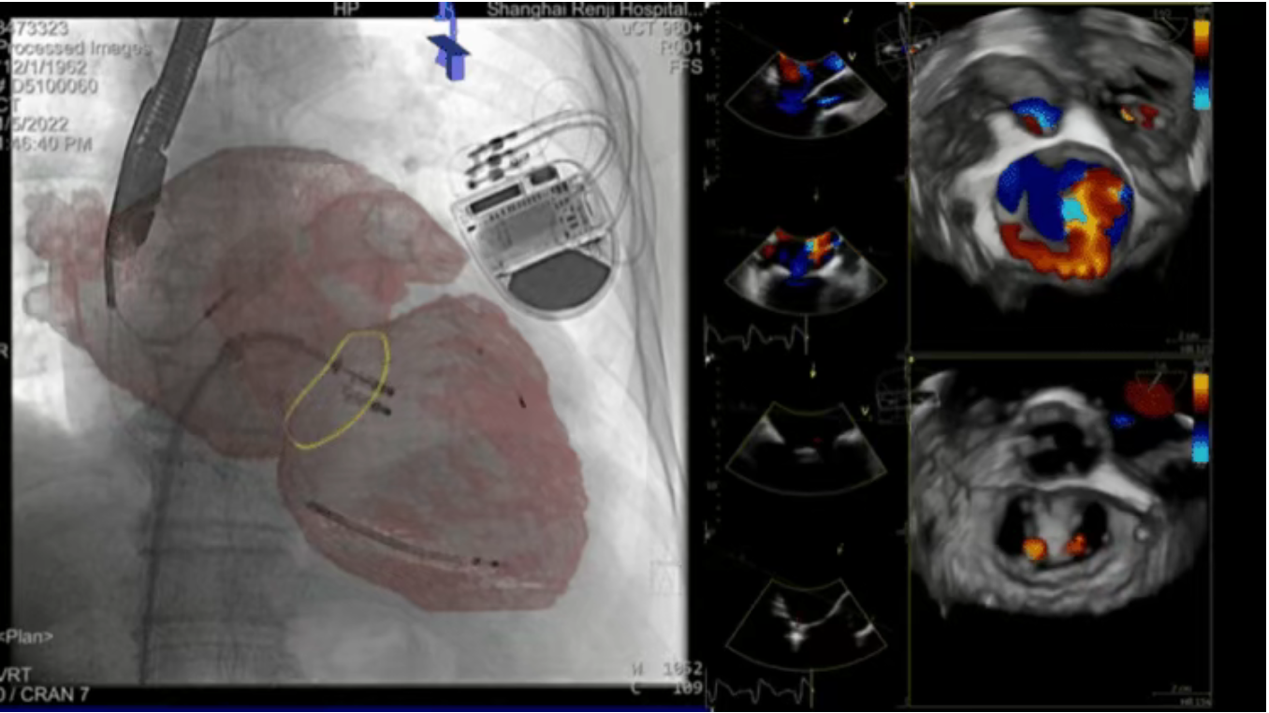

Guided by cutting-edge CTA+CBCT 3D image fusion technology and echocardiography, Professor Pu Jun’s team from the Department of Cardiology first implanted a mitral valve clip to capture and secure the most severe regurgitant area between the anterior and posterior leaflets. Post-clip echocardiography showed near-complete elimination of medial regurgitation, with residual lateral leakage. A second clip was then deployed parallel to the first, effectively resolving the severe mitral regurgitation. Subsequently, the team implanted a left atrial appendage closure device under image fusion guidance. The procedure concluded successfully, with the patient’s physiological parameters stabilizing and recovery progressing smoothly.

One-Stop Minimally Invasive Cardiac Intervention Guided by Precision Image Fusion Technology